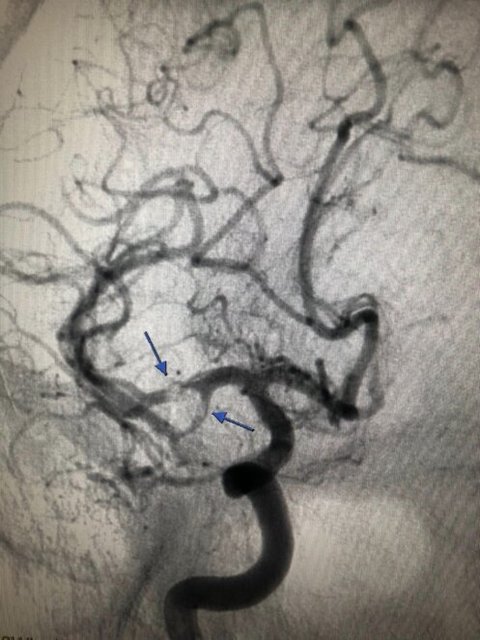

В ургентном порядке, в операционной выполнена инвазионная церебральная ангиография, при которой выявлены тромбы в правой средней мозговой артерии, препятствовавшие нормальному мозговому кровообращению.

С целью предупреждения смерти мозга и для сохранения жизни больного, с помощью современных технологий (внутрисосудисто) — тромбы извлечены из средней мозговой артерии, мозговой кровоток восстановлен.